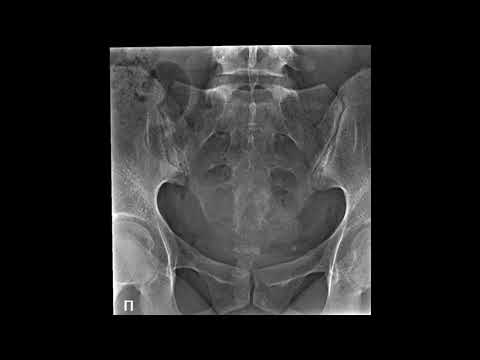

Укладки костей таза и тазобедренных суставов для задней прямой проекцииСкачать